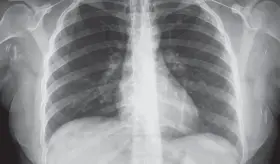

Radiólogo especialista destaca la importancia de la visión independiente del profesional en imágenes diagnósticas para detectar fibrosis pulmonar progresiva y guiar tratamientos específicos según cada patología autoinmune.

Muchas enfermedades pulmonares intersticiales pasan desapercibidas porque sus síntomas imitan a los del asma o la EPOC. Esta confusión retrasa el diagnóstico y pone en riesgo la vida del paciente.